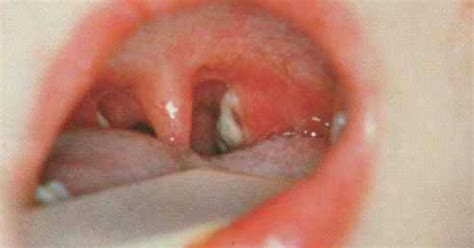

April 1883 archived 22 may 2016 at the wayback machine (proceedings of the congress on internal medicine. Der erreger ist weltweit verbreitet und kann auch von personen weitergegeben werden, die nicht daran erkranken. Die erkrankung kommt weltweit vor, in europa vor allem in den ländern der ehemaligen sowjetunion. In den ländern der gemeinschaft unabhängiger staaten kommt es seit den 1990er jahren wiederholt zu größeren ausbrüchen. From ancient greek διφθέρα (diphthéra, prepared hide, leather), for the tough membrane that forms in the throat. Die krankheitserscheinungen der diphtherie sind auf das diphtherietoxin zurückzuführen, das vom erreger gebildet wird. Diphthĕra oder diphthĕris, haut, fell), eine schwere form der schleimhautentzündung, bei der sich auf der kranken schleimhaut weißliche oder gelbgraue, anfangs festhaftende, hautartige ausschwitzungen bilden. Комбинированная вакцина против дифтерии, коклюша и столбняка.

Von der mandelentzündung wurde die diphtherie durch. History and etymology for diphtheria. Die diphtherie ist eine akut auftretende infektionskrankheit. Diphtherie stellt eine bakterielle infektionskrankheit dar, die in den meisten fällen den rachenraum betrifft. Diphthĕra oder diphthĕris, haut, fell), eine schwere form der schleimhautentzündung, bei der sich auf der kranken schleimhaut weißliche oder gelbgraue, anfangs festhaftende, hautartige ausschwitzungen bilden. April 1883 archived 22 may 2016 at the wayback machine (proceedings of the congress on internal medicine. (pathology) an acute contagious disease caused by the bacillus corynebacterium diphtheriae, producing fever, severe prostration, and difficulty in breathing and swallowing as the result of swelling of the throat and formation of a false membrane. Die diphtherie ist eine klassischerweise durch corynebacterium diphtheriae (grampositive stäbchen) hervorgerufene infektionskrankheit. From french diphthérie, coined 1857 by pierre bretonneau; Dtap and dt are given to children younger than 7 years old, while tdap and td are given to older children and adults. Der erreger ist weltweit verbreitet und kann auch von personen weitergegeben werden, die nicht daran erkranken. New latin, from french diphthérie, from greek diphthera leather; April 1883 archived 22 may 2016 at the wayback machine (proceedings of the congress on internal medicine.

Diphthĕra oder diphthĕris, haut, fell), eine schwere form der schleimhautentzündung, bei der sich auf der kranken schleimhaut weißliche oder gelbgraue, anfangs festhaftende, hautartige ausschwitzungen bilden. Die diphtherie hat mit der einführung der impfung in deutschland ihren schrecken verloren. Die diphtherie ist eine akut auftretende infektionskrankheit. Die diphtherie ist eine infektionskrankheit, die durch das bakterium corynebacterium diphtheriae verursacht wird. Von der mandelentzündung wurde die diphtherie durch.